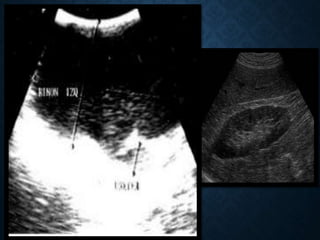

Indicaciones de los Ultrasonidos

 Masa Renal: diferenciación de

masas solidas y liquidas

 Masas quísticas

 Enfermedad medica renal

 Hidronefrosis

 Patología fetal (anomalías del

tracto urinario)

 Anomalías congénitas

 Evaluación del espacio perirrenal

 Próstata: tumores vesicales

 Testículo